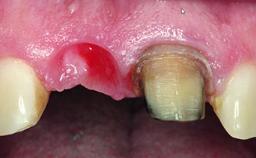

A healthy 28-year-old female patient presented for a consultation on treatment options to restore her upper right central incisor. At the clinical examination, the tooth responded to percussion and palpation. The gingiva was red and slightly swollen, with a mid-facial probing depth of 10 mm. The upper right lateral incisor showed no signs or symptoms, did not respond to exploration and percussion, and the vitality test was positive. The periapical radiograph revealed that tooth 11 had been endodontically treated, with no lesion evident at the apex. A small radiopaque calcified structure surrounded by a narrow radiolucent zone (3 × 3 mm) was present at the apex of tooth 12.

Bone Volume Deficient horizontally, allowing simultaneous augumentation